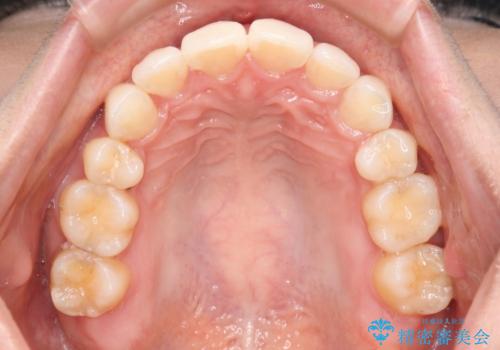

- 歯のガタつきと出っ歯感を治したいとの主訴でご来院され、ハーフリンガル装置を希望なさったため、検査を行ったうえで上下左右4番目の歯を抜歯し歯列を内側に引っ込めつつ叢生の改善を行うこととなりました。

ハーフリンガル装置

ハーフリンガルとは上顎を裏側、下顎を表側のワイヤー装置で治療する場合をいいます。

フルリンガル(上下とも裏側)で治療するよりも費用が抑えられ、治療期間も伸びにくい傾向にあります。また、下顎の舌側に装置がないおかげで口内炎や発音障害もフルリンガルに比べて少ないとされています。